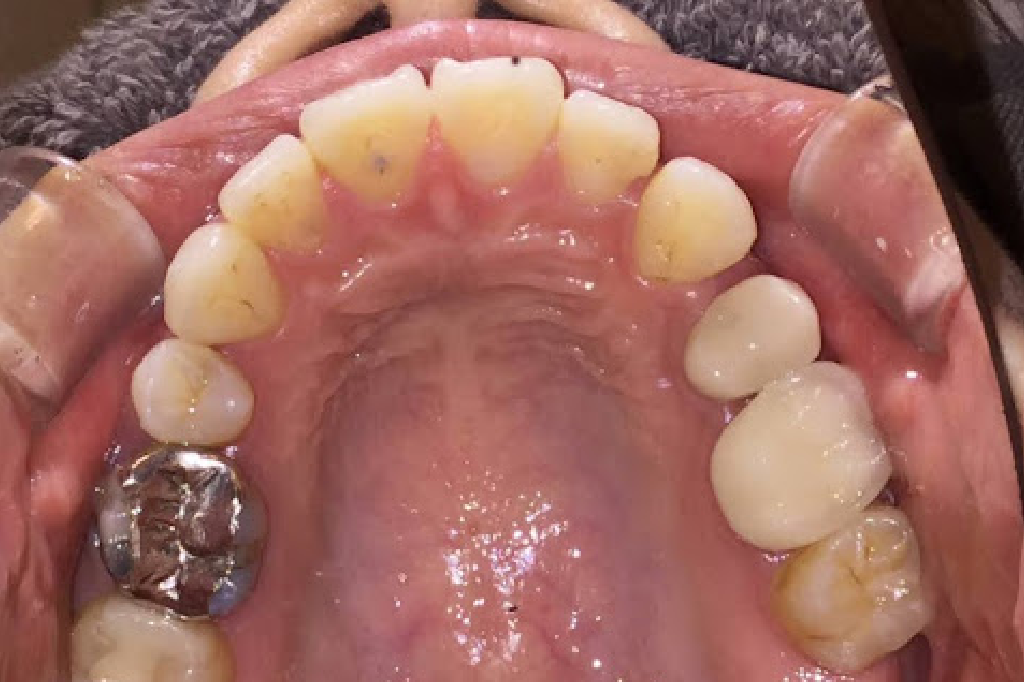

30代女性の歯列矯正

治療後の口腔写真

Before

After

治療プラン:コンプリヘンシブ 追加アライナー:7周(計8周) 便宜抜歯:なし 智歯(親知らず)抜歯:なし IPR:あり 交換日数:約7日